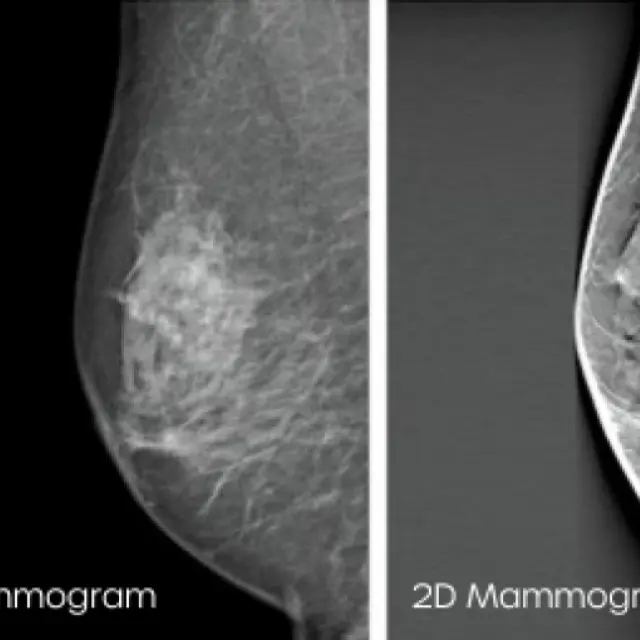

Advanced Breast Screening Technologies

At Auckland Breast Centre (ABC) we utilise the benefits of advanced screening technologies for improved diagnosis and patient outcomes.